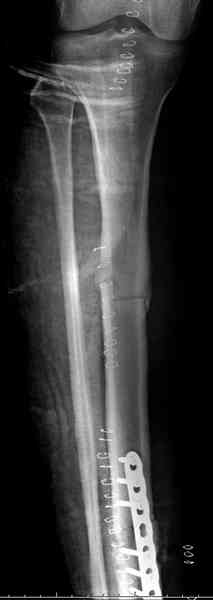

Не оригинальное, подход не раз был демонстрирован нас в стране проф. Анатолием Федоровичем Лазаревым (ЦИТО), который это называет "металлокаркасная пластика". У нас в институте в другом отделении он

помогал сделать несколько таких металлокаркасов, только, насколько я помню, без блокируемых стержней. А в мире эта методика довольно давно

применяется, хотя и не массово. Например, осенью прошлого года на конференции общества Кюнчера в Страсбурге было хорошее сообщение на эту тему. 17 больных, результаты уже до 5 лет.

The cages are commercially available but up to 10 cm. So we measured the needed length on x-rays, added 2 cm at both ends for sure that

the resected piece will include all, and resulted with 15 cm which one was ordered and individually made by the same factory. So yes, we made the gap to fit the cage.

The inner diameter of the tube is 13 mm, the nail was 12 mm, so not so much space to put something inside. Yes, this is really shaft endoprosthesis which i hardly ever would offer for a young football player. Though... Maybe we would when we collect some experience with this sort of implants to feel/prognose its strength in different settings.

No problem with the skin since the cage is less than the removed tissue and the surgery was quick enough not to meet oedema.